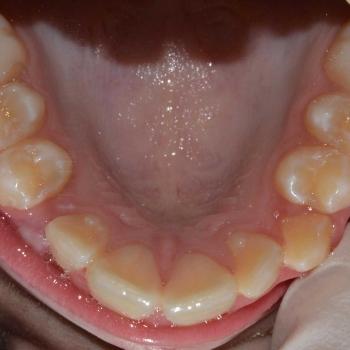

Kíra és édesanyja egy kollegám javaslatára kerestek fel a rögzített fogszabályzó számára legoptimálisabb időszakban, a tejfogak leváltása után, de még a 7-es fog előtörése előtt. Az első konzultáció alkalmával fény derült az alsó és felső fogív nagymértékű torlódására, a jobb felső szemfog kiszorult helyzetére és következményes felső középvonal eltolódására, illetve az enyhe mélyharapásra. A röntgenek kiértékelése után ez a kórkép kiegészült az alsó és felső metszőfogak hátradőlt pozíciójával, ami a kezelést nagyban megkönnyítette, mert lehetőséget adott mindkét fogív meghosszabbítására, így helynyerésre a torlódott fogazat számára.